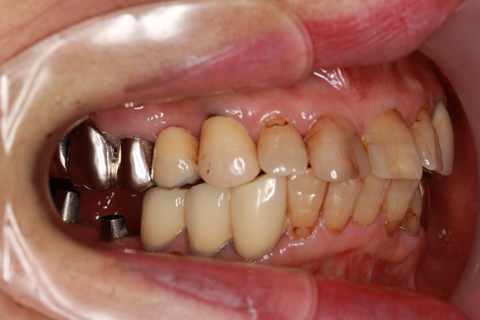

症例2

治療前

インプラント埋入時

治療後

- 年齢・性別

- 57歳男性

- 治療期間

- 3ヶ月

- 抜歯

- なし

- 治療費

- 154万円

- 備考

- 左上5.6.7 及び左下6.7欠損

- 治療内容

- 左上5.6.7と左下6.7欠損部にインプラント埋入

- 施術の副作用(リスク)

- オペによる知覚障害。インプラントによる歯肉炎。インプラント脱落。